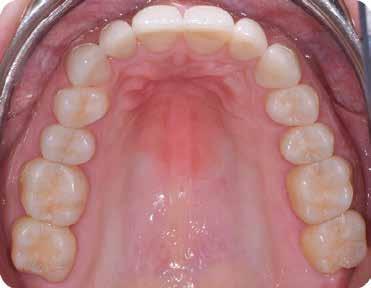

A fogászati kezelések során manapság már nem kizárólag az esztétikai megjelenés helyreállítására törekszünk. Sokszor a kedvezőtlen esztétikai megjelenés hátterében álló okok következményes módon a fogazat funkcionális működését is károsítják, így a kezelések során ezeknek a helyreállításával is foglalkoznunk kell. A különböző funkcionális és esztétikai diszkrepanciák kezelésére számtalan módszer létezik, ám ezen fogászati beavatkozások mindegyikében közös, hogy a kivitelezésük során nagyon szoros együttműködésre van szükség a kezelést végző fogorvos és a munkáját segítő fogtechnikus között. Az alábbi esetbemutatás során egy fiatal hölgypáciens fogazatának héjak alkalmazásával történő esztétikai és funkcionális rehabilitációját szeretnénk ismertetni.

A 19 éves hölgypáciens azzal a kéréssel jelentkezett a rendelőnkbe, hogy szebb fogakat szeretne. Az első konzultáció alkalmával megkérdeztük, hogy mi zavarja leginkább a fogazatának jelenlegi megjelenésében, valamint azt is megbeszéltük vele, hogy milyen végeredmény elérése esetén lenne maradéktalanul elégedett. Ebben az esetben a kezelési célokat az alábbiakban határoztuk meg:

A páciens fogazata esztétikai megjelenésének és funkcionális működésének a lehető legtöbb, saját foganyag megtartása mellett történő helyreállítása (1. és 3. ábra).

A kezelés megtervezése során kifejezett jelentősége van annak, hogy jó kommunikáció legyen a páciens, a fogorvos és a fogtechnikus között. A páciens leendő fogazatának természetes megjelenését a kezelésben részt vevő team szakmai felkészültsége, gyakorlati tapasztalata és a kezelés sikerességének irányába történő elkötelezettsége biztosítja. A beavatkozások megkezdése előtt megtörtént a páciens anamnézisének a felvétele, valamint a klinikai kivizsgálását is elvégeztük. Ezt követően lenyomatokat készítettünk a kiindulási állapotról, majd a kiindulási helyzetet extra- és intraorális fotók segítségével is rögzítettük (13. a-c. ábra).

A tényleges protetikai ellátás megkezdése előtt a páciens mosolygás közben látható fogait otthoni fogfehérítés keretei között a kérésének megfelelő A1-es fogszín eléréséig fehérítettük. A fehérítés során a későbbiekben héjakkal ellátásra kerülő fogak színén nem változtattunk. A fogak előkészítése részeként csupán a két felső nagymetsző (1.1,2.1) incizális élét kellett kismértékben redukálni. A többi felső front fog (1.3,1.2,2.2,2.3) nem került preparálásra.